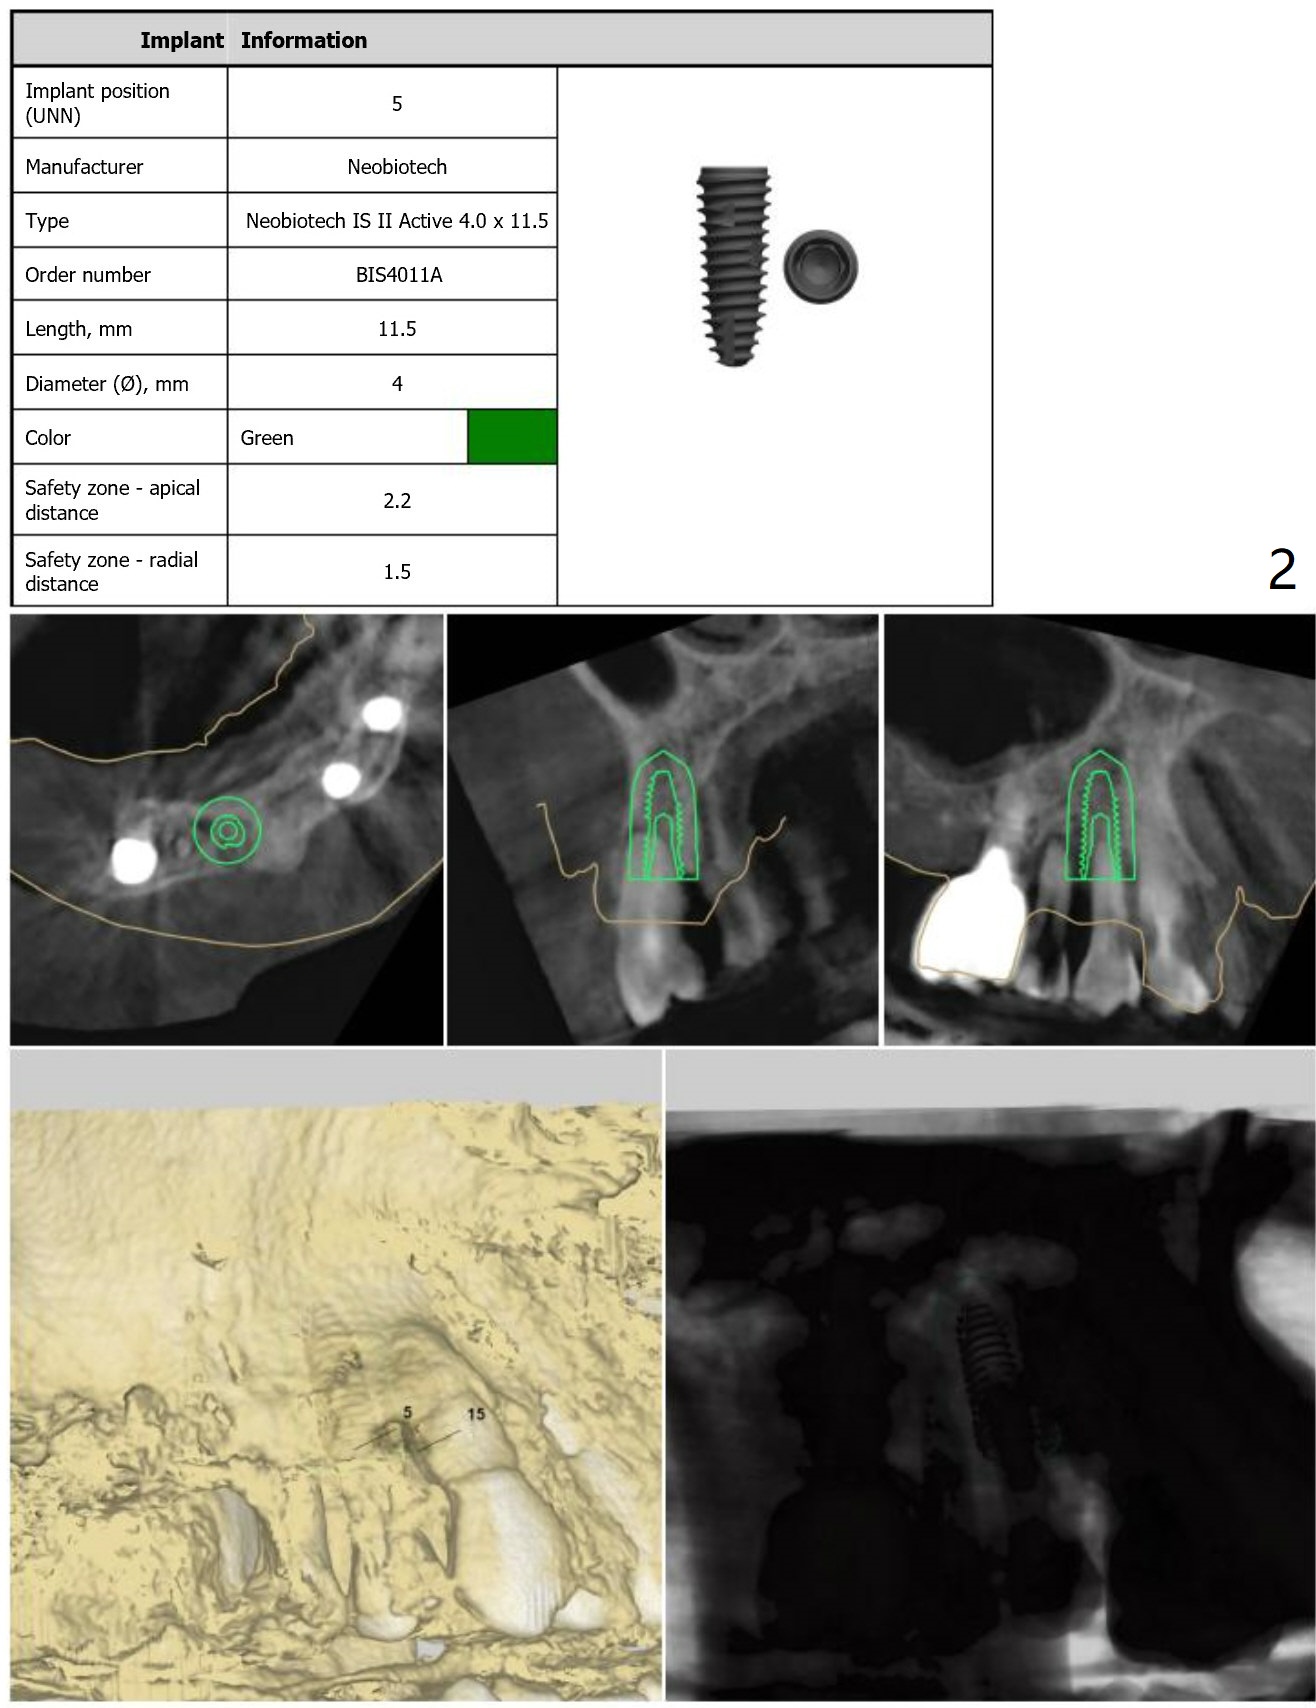

Because of the narrow space at #4 and 5, an implant will be placed slightly distal of #5 site and a cantilever FPD will be made at #4 and 5.